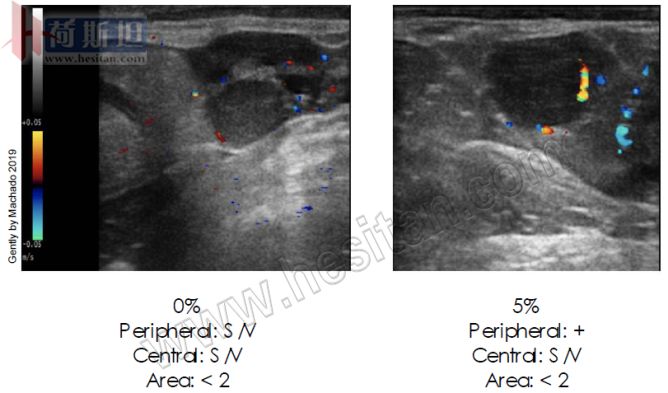

前面两种再同期方案对于空怀牛在100天内可以给牛输精3次,提高怀孕率。近几年,我们又开发了使用彩色多普勒的再同期方案,效率更高。这个方案在输精后16天给牛安置阴道栓,然后7天后从牛体内摘除,使用多普勒检查牛子宫的情况,对于空怀牛注射250-350IUeCG+0.5EC+PG,48h给牛定时输精。

这种技术与前面提到的超声波检查的目标不同,使用彩色多普勒主要是确定牛没有怀孕。对于空怀牛,这个方案每25天可以给牛输精一次,大大提高输精效率。

黄体功能评估

空怀母牛

可能会怀孕